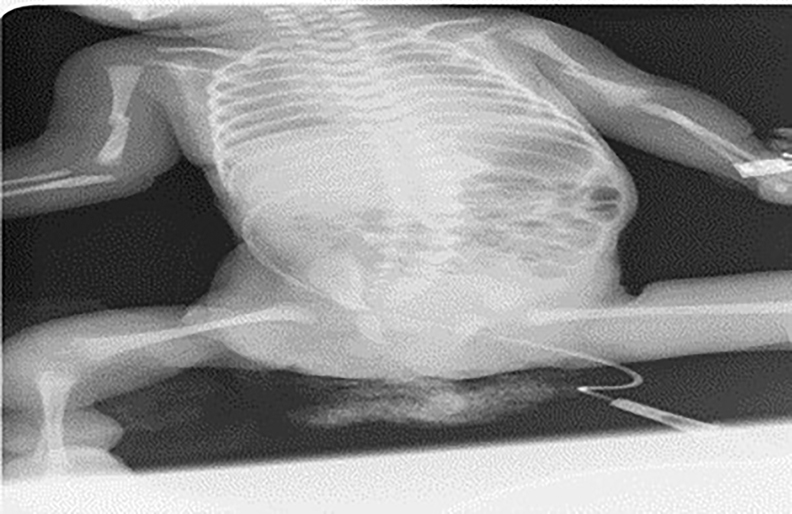

A female infant was born by cesarean section at 33rd gestational week with a birth weight of 1,535 g as the fourth living child of the fourth pregnancy of a 27-year-old mother who did not attend regular antenatal follow-up visits. The patient was admitted to the neonatal intensive care unit with low birth weight, respiratory distress, and structural limb anomalies. In postnatal physical examination, she was found to have hypoactive primitive reflexes, hypotonia, a dysmorphic face appearance, a protruding forehead, short neck, low ear and hairlines, micrognathia, and bluish discoloration of sclerae in addition to the signs of respiratory distress. She had flexion contractures in the distal joints of both upper limbs, developmental dysplasia and flexion contracture in the hip joint, and bilateral pes equinovarus deformity, which are suggesting those are caused by intrauterine amniotic bands. There were two constrictive rings in the distal part of her right lower limb that were caused by an amniotic band in the intrauterine life; she also had an increased skin thickness, edema, and restricted mobility in the dorsum of the right foot. When the patient was evaluated multidisciplinary by orthopedics, radiology and plastic and reconstructive surgery, they were of the opinion that there was no deterioration in blood circulation and there was sufficient blood flow with Doppler ultrasound was performed, that is why there was no need to surgery. In the subsequent clinical follow-ups, it was observed that his circulation became more relieved, and no undesirable events developed. There was thoracic convex scoliosis to the right in the vertebral column. The cystic structure found in the umbilical cord was an umbilical cord cyst. She was free of any limb fracture in her initial examination (Figure 1). She had no familial history of consanguineous marriage, and her father, mother, and the other children of the family were free of any known structural or genetic disease.

Constructive rings and structural anomalies due to amniotic band syndrome and osteogenesis imperfecta.